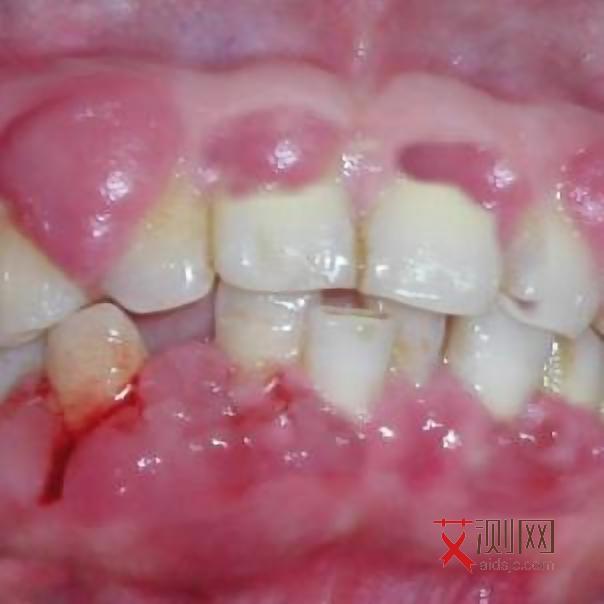

症状表现:反复口腔念珠菌感染、带状疱疹、持续性腹泻、体重下降等。